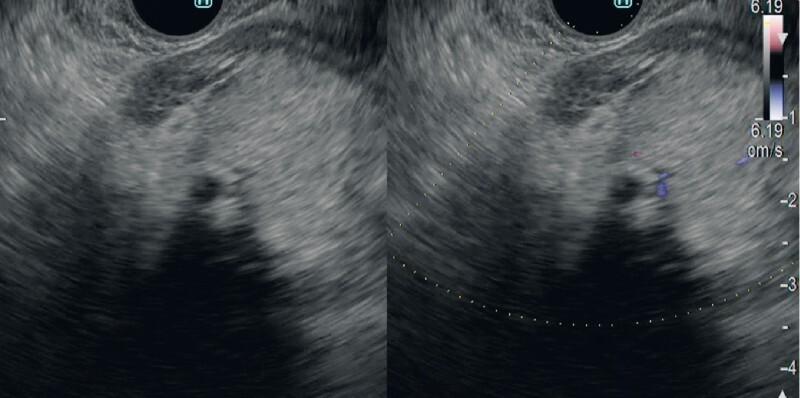

Diagnosis of an intraductal papillary neoplasm of the bile duct with fibrovascular stalks using detective flow imaging.

Endoscopy. 2023 Dec;55(S 01):E1012-E1014. doi: 10.1055/a-2134-9350. Epub 2023 Aug 30.